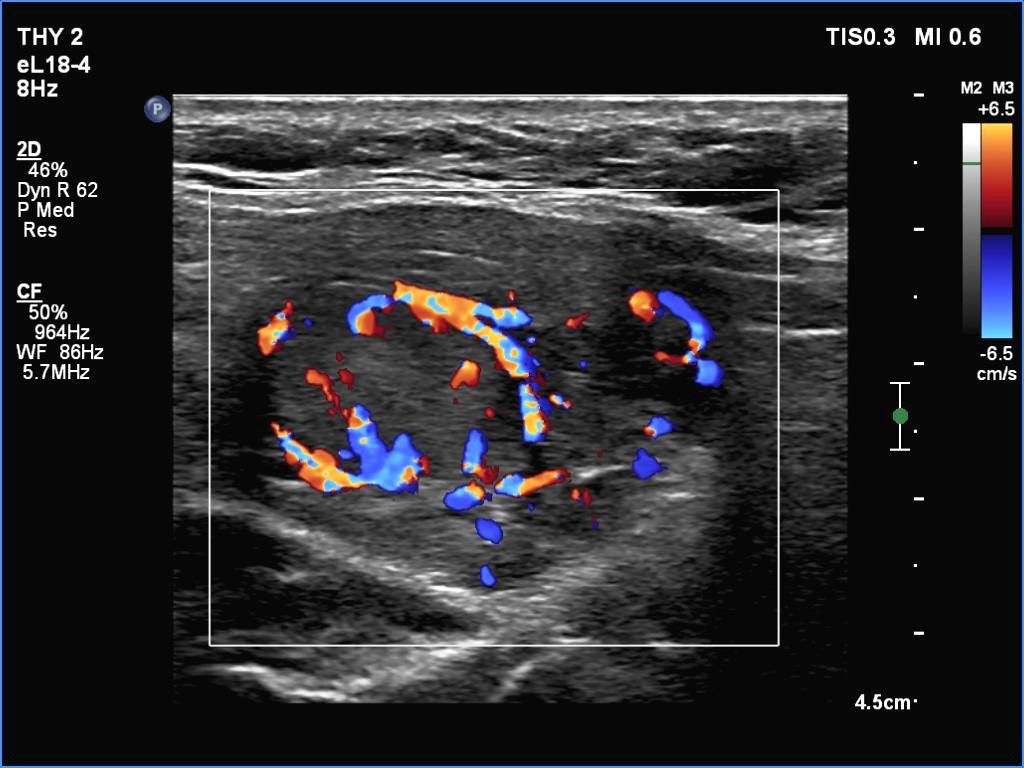

Ultrasonography. The thyroid was partly minimally/moderately, partly very hypoechoic. There was a nodule in the middle of the left lobe. It was lighter than the extranodular part but darker than a normal, healthy thyroid.